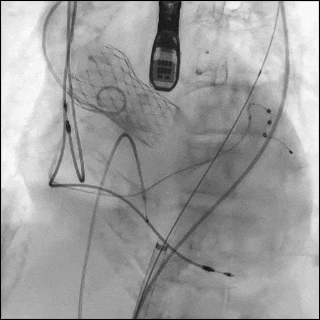

(左图)一名84岁女性因既往植入的 Evolut R 瓣膜出现严重瓣环钙化,接受23 mm S3UR瓣膜行 redo-TAVR。该患者最初因钙化的1型双叶主动脉瓣而植入 Evolut R 瓣膜。(中图)在瓣膜释放过程中,球囊近端发生破裂,远端球囊形成类似“伞状”结构。破裂部位对应严重的瓣上瓣叶钙化区域。(右图)呈伞状的远端破裂球囊无法通过14F鞘管回撤。因此整体取出输送系统及鞘管,将鞘管升级至16F,完成后扩张,并置入覆膜支架修复受损的髂股动脉。

随后植入23 mm S3UR 瓣膜,其流出端与既往瓣膜支架的 node 4.5对齐。球囊扩张过程中发生破裂,导致瓣膜未完全扩张。球囊远端内造影剂积聚提示存在水平撕裂,形成“伞状”结构,使系统无法通过14F鞘管回撤(图6B,视频7)。

经左股动脉将输送系统及鞘管整体取出,随后更换为16F 鞘管以压迫可能的血管损伤。经对侧髂动脉造影显示左侧髂总动脉夹层,但无活动性造影剂外渗(图6C,视频8)。术中血流动力学始终稳定。

随后采用23 mm TRUE 球囊对未完全扩张的 S3UR 瓣膜行后扩张(图6D,视频9)。后TEE提示瓣膜位置良好,无瓣周漏(PVL)。